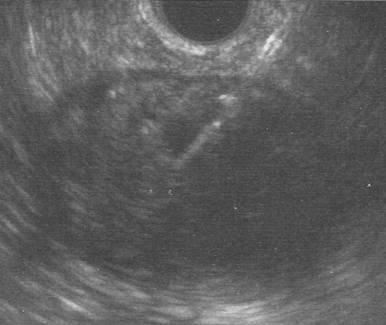

The pancreatic EUS-FNA was performed under conscious sedation with a linear echo-endoscope (Olympus GF-UCT240 and Aloka ProSound SSD-4000, KeyMed, Southend, UK) and a 19G Echotip Ultrasound needle (EUS 19T Cook, Limerick, Ireland). The 3.5 cm part-solid, part-cystic lesion was found in the pancreatic tail. A large amount of white necrotic material was aspirated, however little fluid was obtained (Figure 2). Samples were sent for cytology, cell block and tuberculosis culture for acid-fast bacilli. CEA and amylase were also requested but unfortunately due to the minimal volume of fluid aspirated, these assays could not be performed. Acid-fast bacilli culture was negative.

Figure 2. EUS-FNA image confirming successful puncture of the lymphoepithelial cyst. |